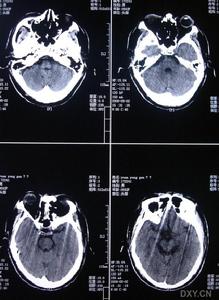

4、CT和MRI顯示額和(或)顳葉不對稱性萎縮。

2、CT和MRI檢查可見特徵性局限性額葉和(或)顳葉萎縮腦回窄腦溝寬及額角呈氣球樣擴大,額極和前顳極皮質變薄,顳角擴大,側裂池增寬,多不對稱少數可對稱,疾病早期即可出現SPECT檢查呈不對稱性額、顳葉血流減少PET顯示不對稱性額顳葉代謝降低,二者較MRI更敏感,有助於早期診斷。目前尚無有效療法主要是對症治療乙醯膽鹼酯酶抑制劑通常無效。對有攻擊行為易激惹和好鬥等行為障礙者,可謹慎地使用小量苯二氮類、選擇性5-HT再攝取抑制劑精神安定劑和普萘洛爾(心得安)等有條件者可住院治療,或由經培訓的照料者給予適當的生活、行為指導及對症處理。